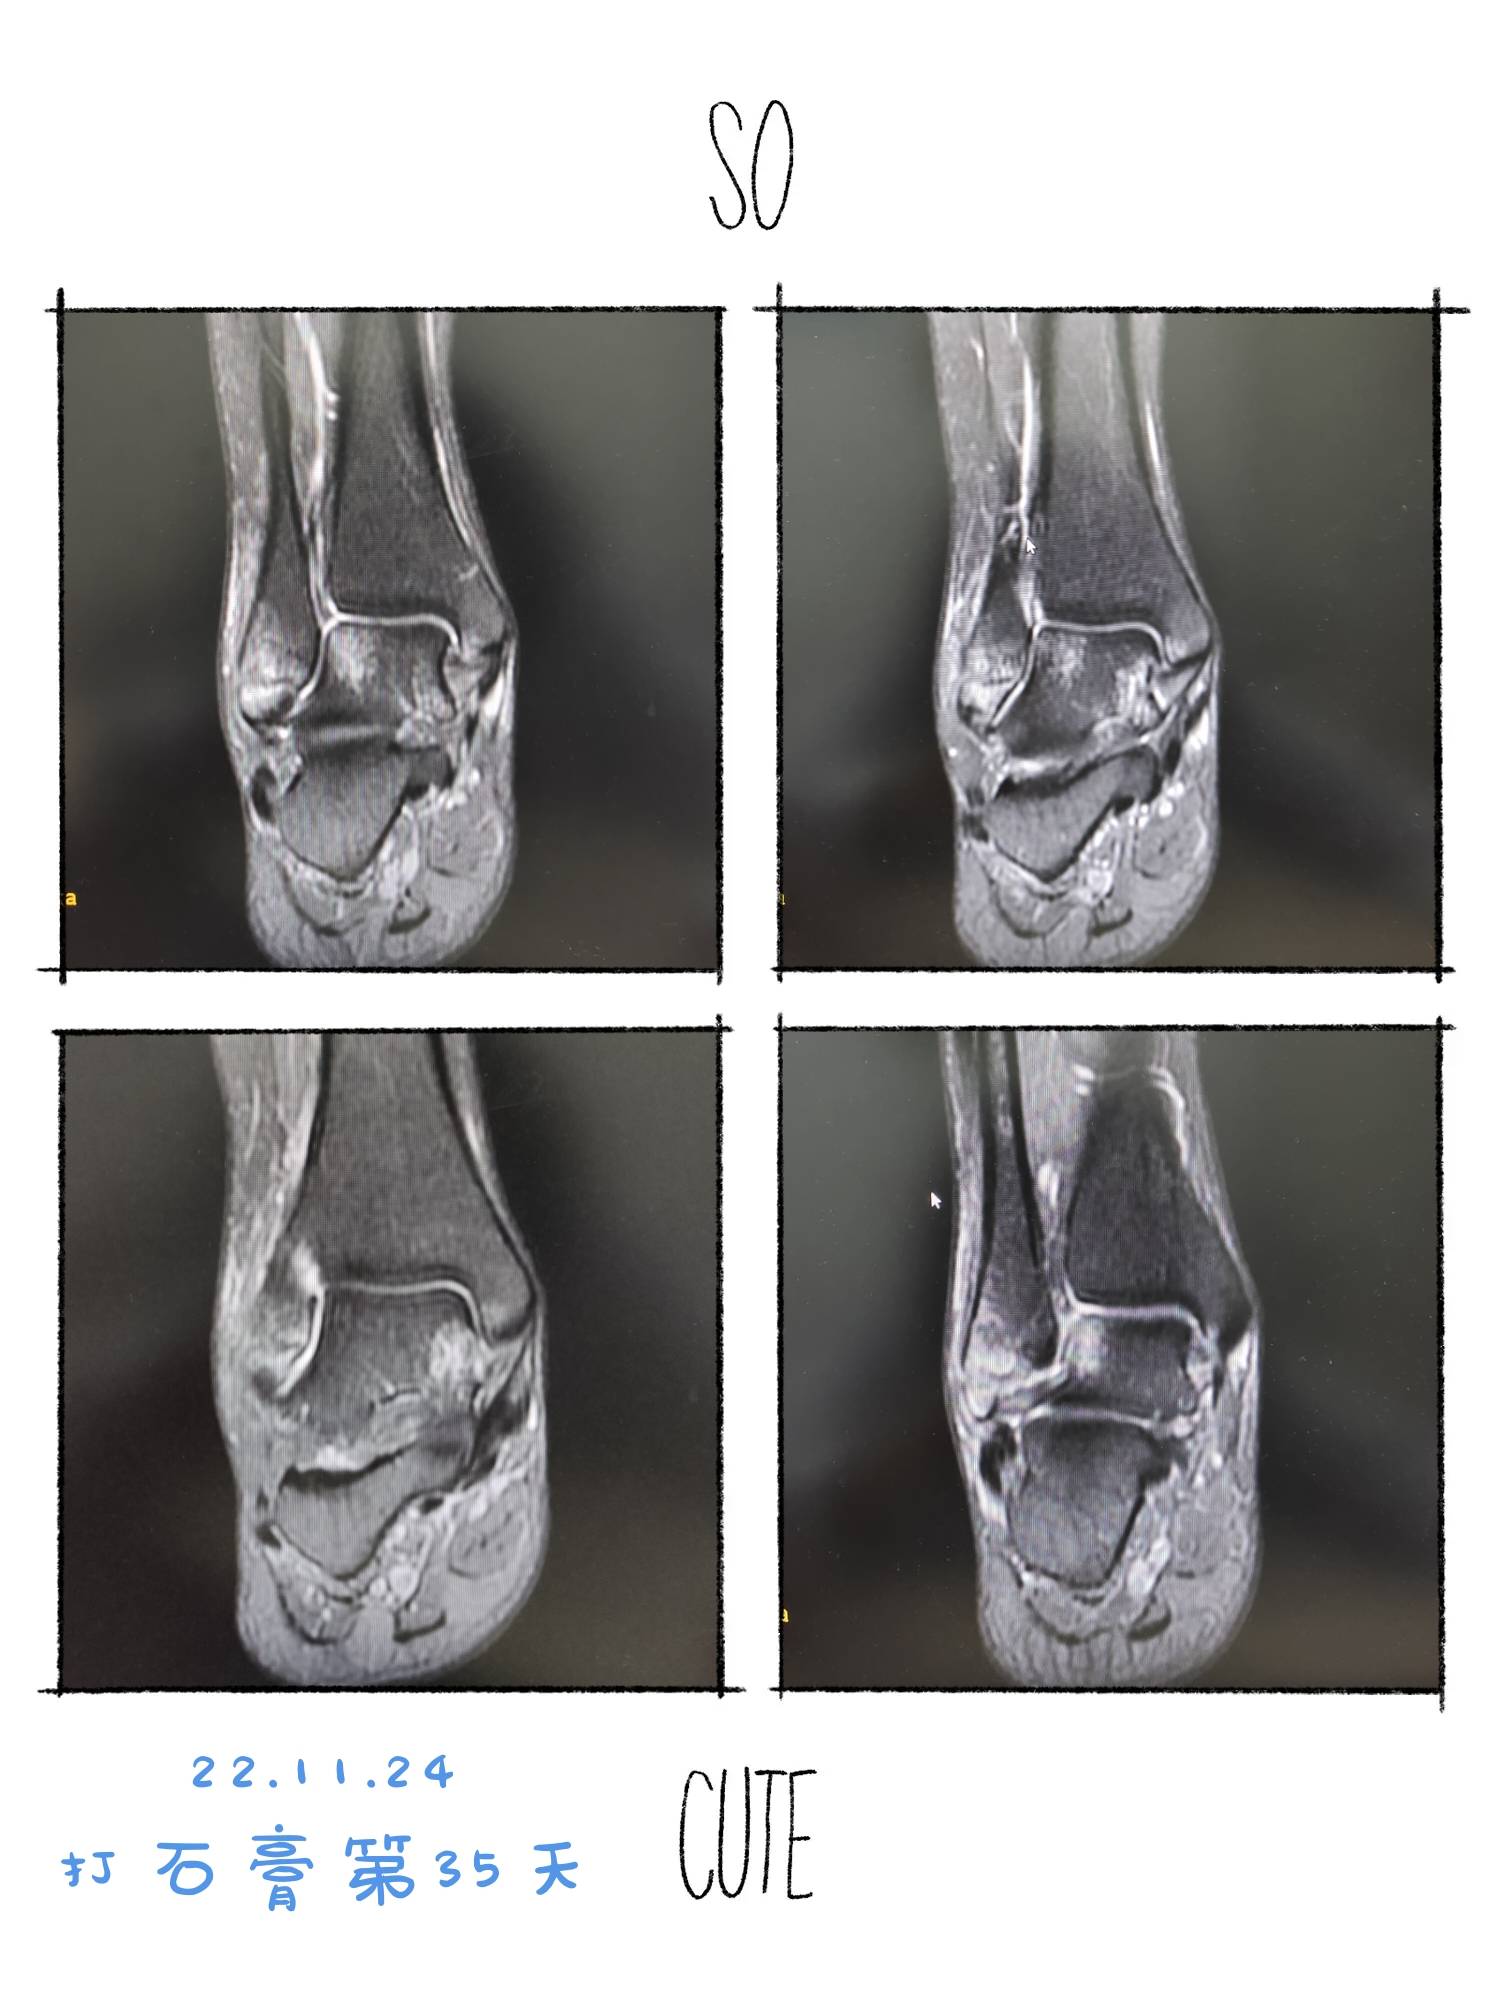

22.11.24踝关节水肿较上次已减少。继续石膏固定,不能负重。医生建议再打两周石膏。